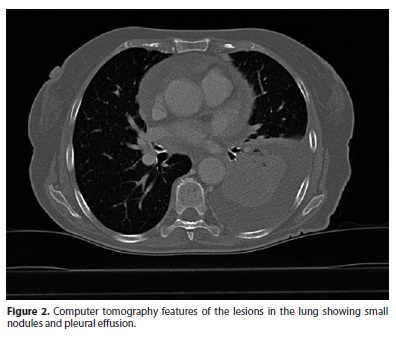

A 71 year-old woman noticed, progressive vision reduction in both eyes. Ocular examination revealed her best visual acuity to be 20/40 RE (right eye) and 20/100 LE (left eye). Results of her slit lamp revealed nuclear cataract in both eyes. Her pupil size and reaction was normal. Her ocular movements were normal in all gazes. Her intraocular pressure was also normal. Fundus examination of the left eye showed an ill-defined, yellow-white elevated lesion in choroid about five times the disc diameter in size (Figure 1). A fundus picture of the right eye was normal. An ultrasonographic evaluation of the eye demonstrated that the tumor had a height 4,1 mm, anterior-posterior length 13 mm and lateral length 12,9 mm. The tumor revealed a dome-surfaced, elevated choroidal lesion with moderated internal reflectivity. Fluorescein angiography showed hiperfluorescence from the surface of her choroidal tumor. The lesion was on its late phase and it had already accumulated subretinal fluid. Routine systemic investigation including complete blood cell count, platelet count, bleeding time, urine analysis, serum electrolytes, blood biochemical studies for hepatic and renal function was carried out A chest x-ray showed a homogenous opaque mass in patient's left hilar area. A computer tomography scan of the thorax revealed a several small nodules in both superior lobe of the lung and pleural effusions. (Figure 2). Transbronchial biopsy revealed bronchioloalveolar carcinoma (Figure 3). At this time the patient also showed bone metastasis. The chemotherapy was not initiated because our patient died after few weeks.